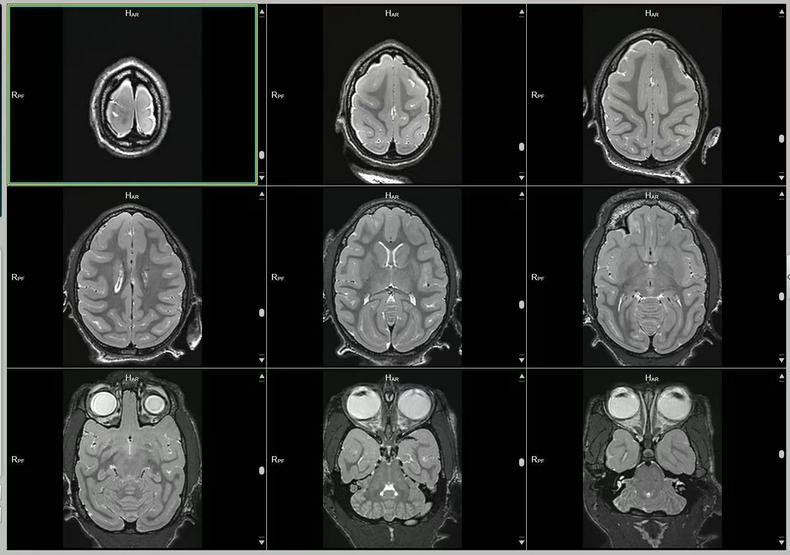

预定本数据集为2023-2025年对2只(15岁、23岁)中年、老年健康雄性猕猴的脑部磁共振扫描收集的数据,主要包括T1w序列和T2w序列影像(3D影像),对于神经学、心理学、行为学等多个相关学科的研究提供丰富的脑数据支撑。

a.物种:猕猴

b.实验动物信息

样本数量:2只

年龄分布:15岁/23岁

重量分布:10-15kg

性别分布:雄性2只

c.扫描仪规格

扫描仪类型:联影uMRNX 3.0T磁共振扫描仪器

线圈:12通道猕猴专用头线圈

d.扫描程序

动物福利伦理:由中国科学院昆明动物研究所实验动物福利伦理委员会批准。

动物护理和饲养:中国科学院昆明动物研究所实验动物中心

麻醉程序:阿托品(0.5mg/ml)-氯胺酮(0.05mg/ml)-丙泊酚(2mg/ml),阿托品和氯胺酮之间间5-10分钟,氯胺酮和丙泊酚之间间隔5-10分钟。

麻醉和扫描间隔时间:从阿托品算起,大约25分钟,从氯胺酮算起大约15分钟。

扫描体位:仰卧头先进